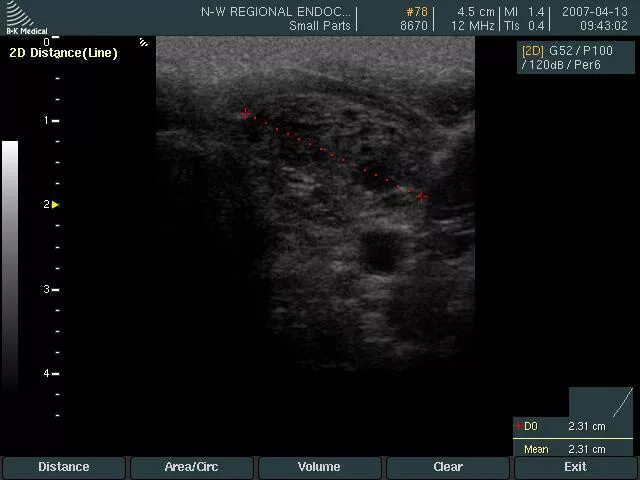

Диффузные изменения щитовидной железы на узи